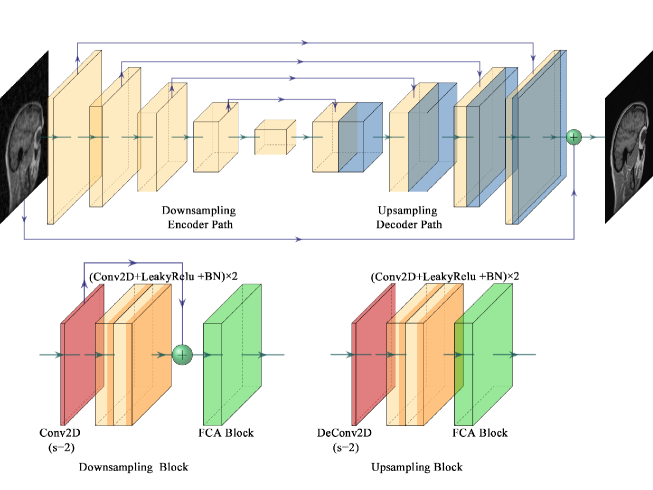

An improved U-Net is proposed as the generator in our proposed PIDD-GAN for higher reconstruction performance, where the generator input is sensitivity-weighted zero-filled image . As shown in Fig. 2, in our improved U-Net, cascaded downsampling blocks are placed in the encoder path (left), and corresponding cascaded upsampling blocks are placed in the decoder path (right). Skip connection and concatenation are applied between the downsampling blocks and the symmetrical upsampling blocks with the same scale to preserve the feature from different levels and, ultimately, yield better reconstruction details.

Fig. 2 shows the downsampling block structure. First, a convolution layer with stride = 2 is applied to downsample the output. Then, a residual block extracts further features and avoids gradient vanishing and exploding problems (He, ). There are two convolution layers in the backbone and a convolution layer adjusting the channel and fusing feature maps at different scales. Leaky ReLU layers and Batch normalisation (BN) are applied after each convolution layer except the final one. Finally, a FCA Block (Qin, ) learns the different channel weights with attention. The structure of upsampling blocks and downsampling blocks are similar. A deconvolution layer with stride = 2 is applied to upsample the output. The shortcut is removed to reduce computation cost but maintain high reconstruction quality here.

Traditional CNNs treat all channels in a feature map with the same importance, ignoring the importance differences. Therefore, the attention mechanism is adopted to make use of importance difference information by learning the different channel weights, i.e., effective channels have high weights and ineffective channels have small weights, which helps to train the model and enhance the results.

FCA Block (Qin, ) is a novel attention mechanism based on the squeeze and excitation block (SE Block) (Hu, ), as shown in Fig. 3. First, an feature map is squeezed into a vector. Then channel weights are extracted by two fully-connected layers, and channel weights multiply the original feature maps. A two-dimensional discrete cosine transform (DCT) is applied in FCA Blocks to squeeze the feature map, rather than global average pooling employed in SE Blocks, since this latter operation is equivalent to the lowest DCT frequency. Hence using only GAP leads to loss of other frequency components in the feature channel containing useful information. In the squeezing step, the feature map is divided evenly into parts (each size is ). The squeezing step can be represented as

where denotes the preset DCT template and denotes the corresponding frequency component. In this work, FCA Blocks are utilised after every residual blocks in the generator.

As the network architecture goes deeper, more granular information can be extracted, but leading to gradient vanishing and exploding problems, making the network converge slowly. The introduction of residual learning (He, ) solves this problem effectively. The main idea of residual learning is the utilisation of shortcut connections between the convolution layer. It makes the deep network easier to be trained and converge faster. Global residual learning (GR) is applied in our improved U-Net. The output of the generator adopts instead of in the original U-Net. This change transfers the generator from a conditional generative function to a refinement function. This work also applies local residual learning (LR) by the shortcut connection in each residual block in the downsampling path. The utilisation of LR aimed to stabilise the training and accelerate the model convergence.